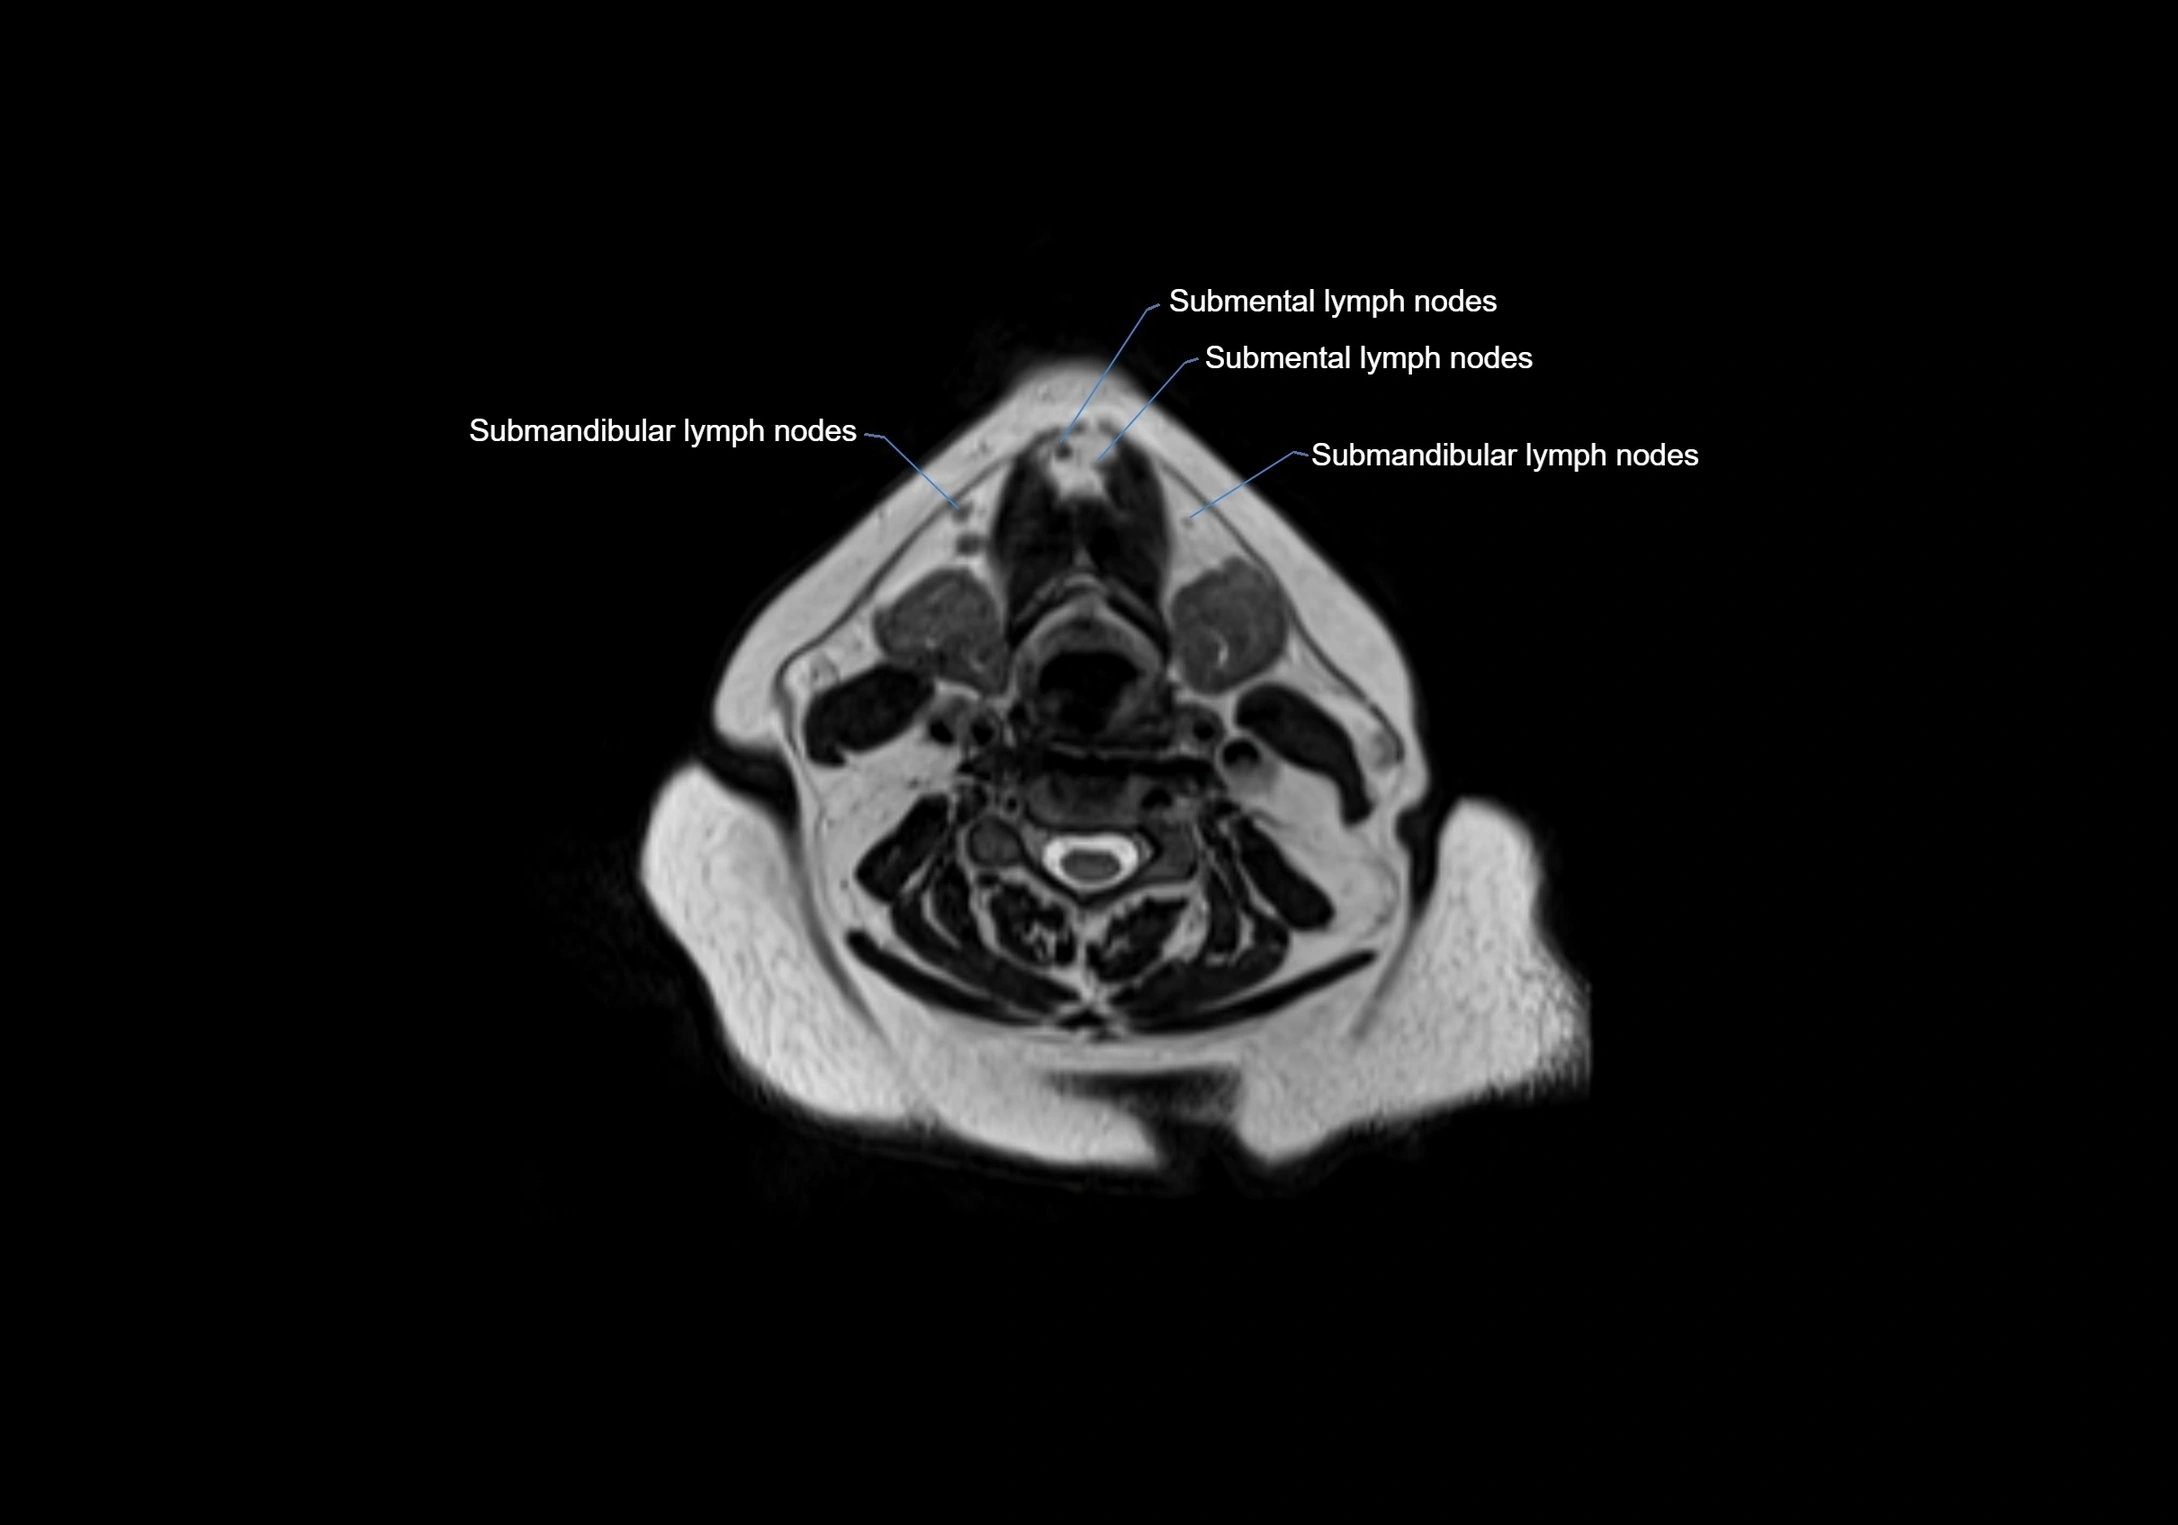

Location

• Found along primary lymph node chains, including preauricular, submandibular, parotid, and occipital regions

• Embedded in subcutaneous fat or superficial fascia, often lateral or posterior to primary nodes

• Variable in number; may occur unilaterally or bilaterally, depending on individual anatomy

MRI images

image